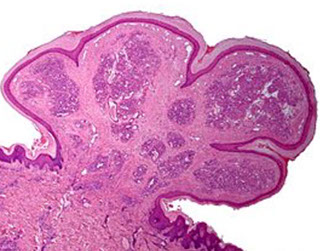

Eccrine poroma

Friable papule/plaque MC on sole/scalp surrounded by indented moat (demarcation); resembles pyogenic granuloma clinically

- or is it found on extremities of middle aged adults??

Micro: monotonous cuboidal/basaloid "poroid" tumor cells in lower part of acanthotic dermis has a broad base that extends into dermis

- sharp demarcation (moat) between normal skin and tumor

- tumor cells may have cytoplasmic clearing due to glycogen accumulation; can also have melanin

- can see small sweat ducts in tumor (vs seb k)

Variations: 1) Hydroacanthoma simplex, 2) Syringofibroadenomatosis, 3) Sebocrine adenoma

1) Basaloid/clear cell clone prolif. w/ lumen of ducts entirely w/in epidermis (like Borst_Jadassohn intraepidermal epithelioma

2) Uncommon, reticular prolif of ducts in dermis that connects to surface ( like fibroepithelioma w/ sweat ducts); may be from Schoepf syndrome

3) Sebaceous + apocrine diff in poroma-ish lesion

IHC: EMA (highlights luminal component of the ducts)

DDx

1) Porocarcinoma (Malig eccrine poroma): rare, larger, more cytologic atypia/necrosis/ invasion; looks like SCC w/ sweat ducts

2) Nodular hidradenoma: looks a lot like eccrine poroma, but w/o the surface connection; but the "poroid cells" look identical

3) Seborrheic keratosis: the basaloid cells may look poroid; but you don't see any sweat ducts

Poroma